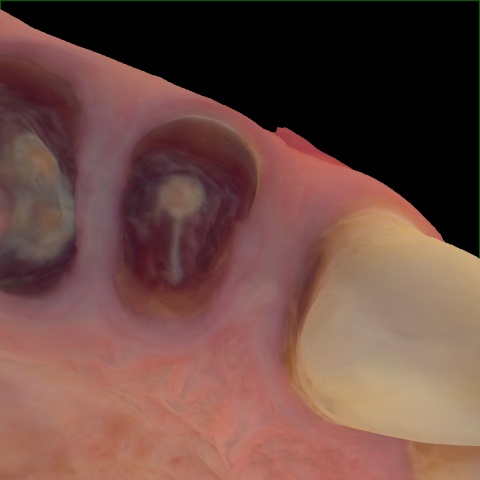

NHD36692

Annotated as "Good"